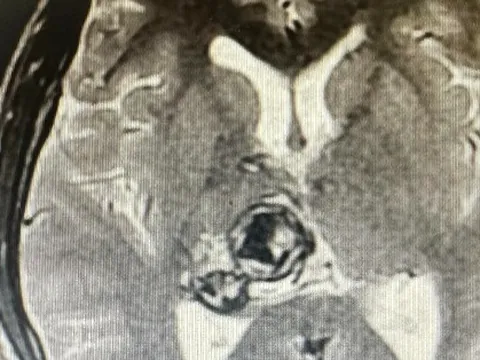

Nam sinh viên 20 tuổi phát hiện khối u não sau khi thấy đau đầu, chóng mặt

Nam sinh viên 20 tuổi thường xuyên có hiện tượng đau đầu, chóng mặt. Đi khám được xác định u não nhưng bị từ chối can thiệp do u nằm sâu trong não.